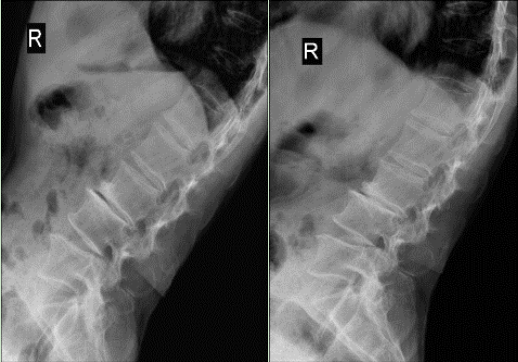

神经脊柱外科主任

主任医师邵世坤接诊后

通过详细查体和病情评估

明确老胡这病

属于巨大脱垂型腰椎间盘突出

压迫局部神经引起剧痛

同时伴有腰椎不稳

邵世坤用椎间孔镜技术

在老胡的脊柱自然空隙(椎间孔)里

置入一个直径不足1cm的通道

直达椎间盘病灶